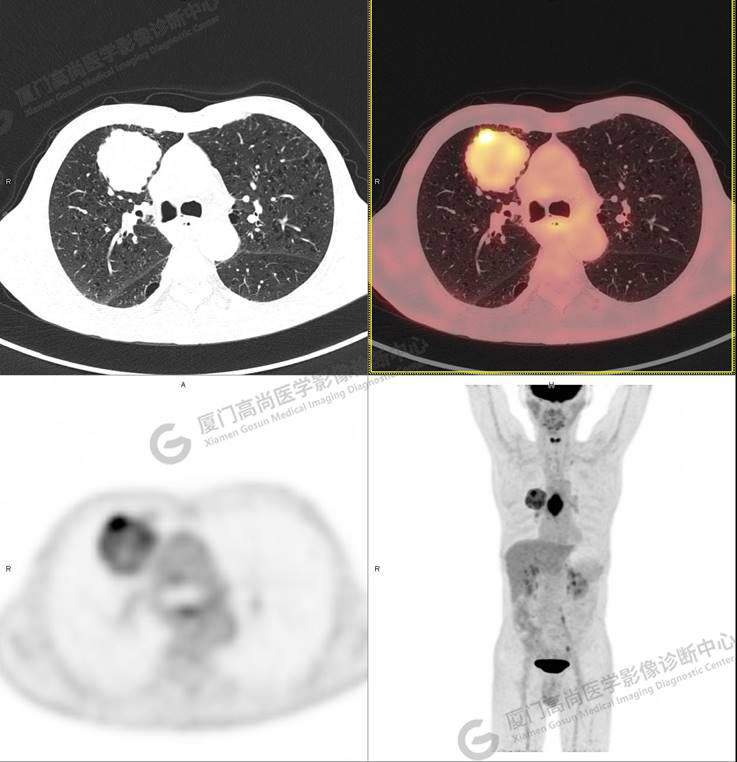

右肺上葉軟組織密度腫塊,大小約5.9×5.5×6.3cm,形態(tài)不規(guī)則,邊緣見棘突,其內(nèi)密度不均勻,放射性攝取不均勻性增高,SUVmax 6.46;腫塊周圍見多發(fā)小結(jié)節(jié)影,較大者直徑約0.6cm,放射性攝取未見明顯增高。影像學(xué)表現(xiàn)考慮右肺癌并肺內(nèi)轉(zhuǎn)移。

同時發(fā)現(xiàn)食管中段管壁增厚,管腔狹窄,放射性攝取不均勻性增高,SUVmax 9.67。